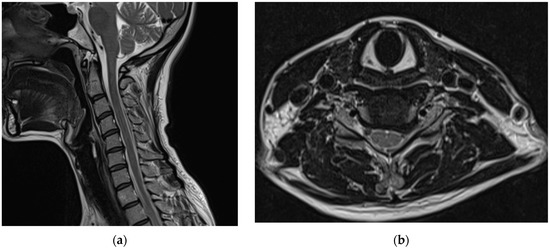

Subsequently, for left C6 impingement, the patient underwent CIESI under fluoroscopy using the C5/6 interlaminar approach. According to the medical records, when the Tuohy needle was inserted epidurally during the procedure, the patient experienced severe pain, described as burning and electric, in the left arm. Subsequently, a mixture of 3 mL of 1% lidocaine and 1 mL of dexamethasone was injected in the epidural space. Immediately after the procedure, the patient was in an alert mental state; however, severe dizziness, reduced blood pressure (BP 60/40), reduction of left arm motor function to motor grade 0, and loss of sensory function other than touch were observed. Blood pressure instability was relieved within approximately 1 h after the procedure with the administration of vasopressors, inotropes, and anticholinergics. However, motor weakness and sensory loss persisted in her left arm. Furthermore, 6 h after the procedure, the patient developed postdural puncture headache (PDPH) with a VAS score of approximately 7, after which she presented to the emergency department of our hospital. At the time of her visit, her vital signs were normal. On the second day of CIESI, the PDPH-related VAS score was 7. Upon physical examination, the manually tested muscle power of the left upper extremity was 2/5 proximally and 3/5 distally. Pressure and temperature discrimination, light touch, and vibration sensations decreased in the left upper arm. The remaining extremities and facial areas had intact motor and sensory functions. The patient complained of severe PDPH; therefore, the presence of gait disturbances could not be confirmed. Contrast-enhanced brain and cervical spine MRIs were performed on the second day of the procedure. After brain MRI, the assessment by the radiologist was of a “probable small amount of parafalcine subdural hematoma (SDH), left” (Figure 2).

Figure 2.

Brain magnetic resonance images obtained on the second day of the procedure: (a) T2-weighted sagittal image and (b) T2-weighted axial image. The assessment by the radiologist was of a “probable small amount of parafalcine subdural hematoma, left.” However, clear findings indicating a subdural hematoma are absent.